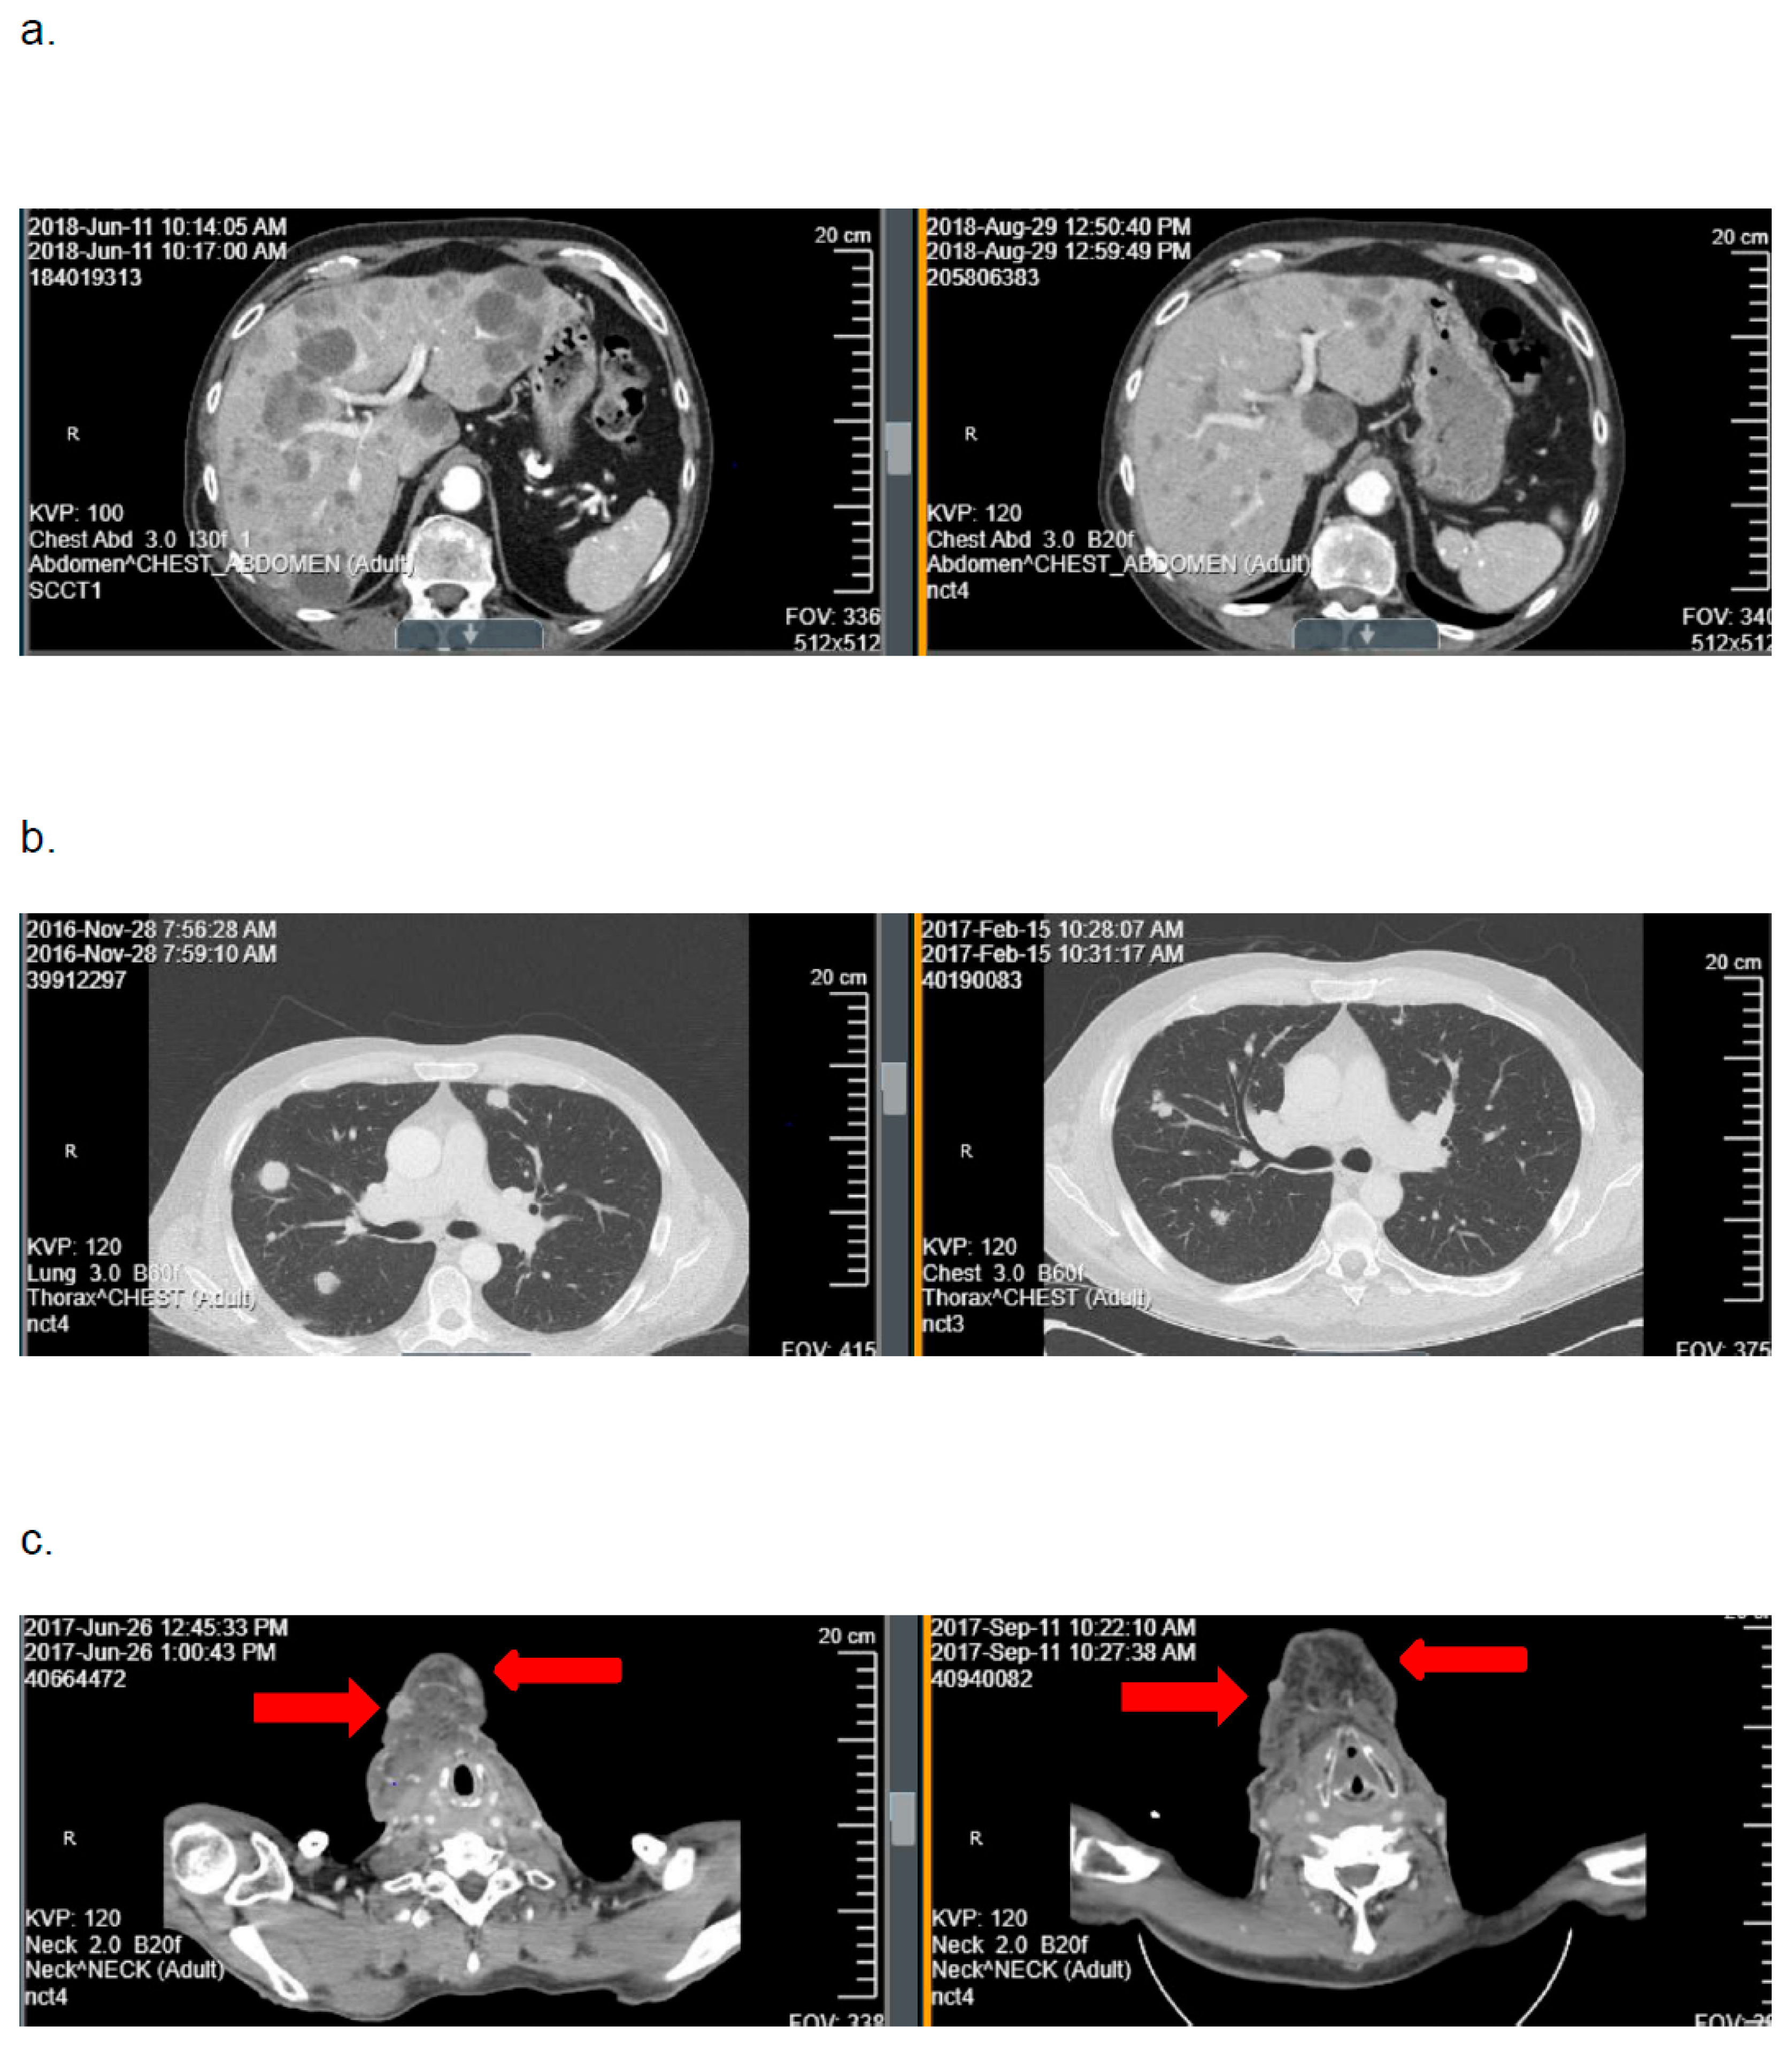

In cohort A, the ORR was 9.1% (95%CI: 0–19.4). Best tumor response included PR in 3 patients (9.1%), SD in 10 (30.3%), and PD in 20 (60.6%). One response was confirmed and two responses were unconfirmed (Figure 2). As seen in Figure 3, the depths of these partial responses were significant. The DoR’s were 2.3, 2.5, and 4.5 months. In cohort B, the ORR was 0%. The best tumor response included SD in three patients (25%) and PD in nine (75%).

Figure 2.

Representative examples of computed axial tomography imaging scans obtained at baseline (left) and after two cycles of mitomycin-C (right) from the three patients on cohort A with a tumor response with mitomycin-C: (a) patient 21: hepatic metastases, (b) patient 10: pulmonary metastases, and (c) patient 14: subcutaneous metastases.

In this trial, the primary hypothesis of achieving an ORR of ≥30% with mitomycin-C was not met in either cohort. The ORR was 9.1% among patients with HPV-positive, platinum-refractory RM-HNSCC (cohort A) and 0% among patients with HPV-negative, platinum-refractory disease (cohort B). Although three patients in cohort A experienced deep tumor responses with mitomycin-C (Figure 2 and Figure 3), the DoRs were brief (≤4.5 months). Based on these data, further investigation of mitomycin-C as monotherapy in patients with biomarker-unselected, platinum-refractory RM-HNSCC is not warranted.